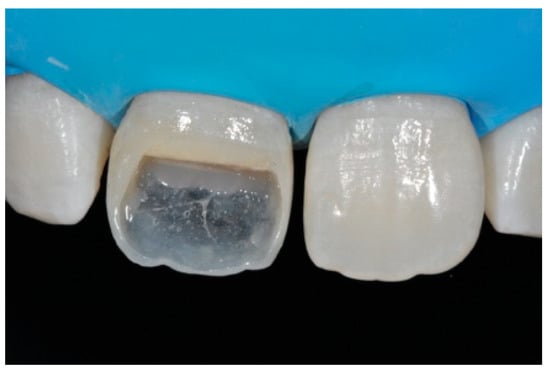

Once completed, the two frames (Clearfil Majesty ES-2, A1E, A2D, Kuraray Noritake Dental, Tokyo, Japan) showed internal and external excesses that were reduced using diamond burs and discs (Figure 33 and Figure 34) strictly following the procedure described in Section 2.1.2 of present article. Excesses were removed from the distal-incisal angle of #2.1 allowing therefore to obtain the desired translucency. After silane application and bonding procedure (Figure 35) as described in Section 2.1.2, restorations were completed (Figure 36 and Figure 37). They both show satisfactory clinical integration 1.5 years post-operative (Figure 38 and Figure 39).

Figure 33.

Frame imprecisions are corrected by reducing interproximal wall from the internal side. Reprinted from Restauri diretti nei settori anteriori, G. Paolone, S. Scolavino, © 2021, with permission from Quintessence Publishing Italy.

Figure 34.

Frame is also trimmed reducing external outline. Reprinted from Restauri diretti nei settori anteriori, G. Paolone, S. Scolavino, © 2021, with permission from Quintessence Publishing Italy.